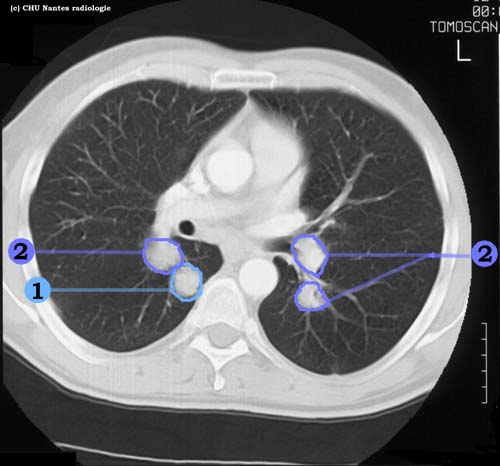

Lésions nodulaires : coupe TDM

1 . opacités nodulaires hilaires : adénopathies

2 . opacités nodulaires solides bilatérales à contours nets en lâcher de ballons